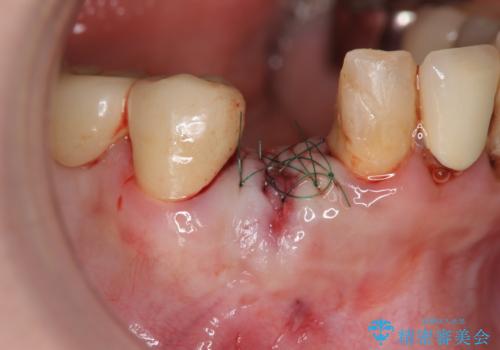

X線写真および歯周組織検査より、歯の破折 周囲骨の高度な吸収が認められました。

抜歯後、インプラントによる審美・機能改善を希望されたのでインプラント埋入に先立ち吸収した骨の再生を計画します。

歯を失う原因が虫歯や根尖病変などはなく、歯周病や歯の破折等周囲の骨を吸収する原因の場合はインプラント治療を行うに先立ち骨の造成が必要なことがあります。